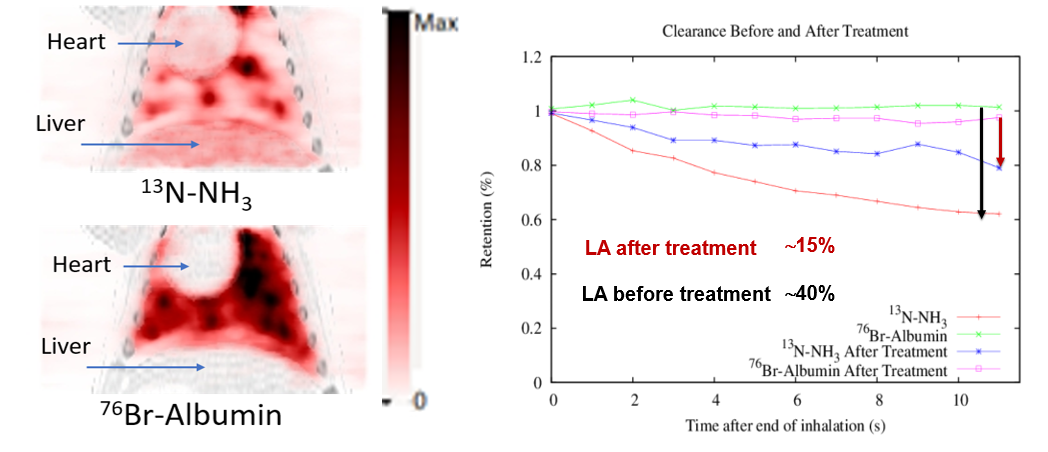

| ABSTRACT | Multiplexed PET (mPET) is a new imaging technique compatible with any existing PET scanner which allows simultaneous imaging of two PET tracers in vivo. In this work we present initial results of a new procedure to measure liquid absorption (LA) in the airways, a promising biomarker for evaluating treatment response in lung diseases. We performed dynamic PET imaging in the lungs of 10 pigs in a clinical PET scanner using inhaled 13N-NH3 and 76Br-Albumin as tracers.

Triple coincidences in PET can be used to enable the simultaneous imaging and separation of radiotracers labeled with standard positron emitters (such as 13N) and positron-gamma emitters (such as 76 Br). We have previously shown that multiplexed PET can be achieved without any kinetic modelling or hardware modification, and therefore it can be used in most current PET scanners. The goal of this study was to demonstrate that this methodology can be applied to solve important clinical needs, such as the quantitative measurement of the liquid absorption in the airways, a new biomarker for the treatment response of Cystic Fibrosis (CF) patients. |